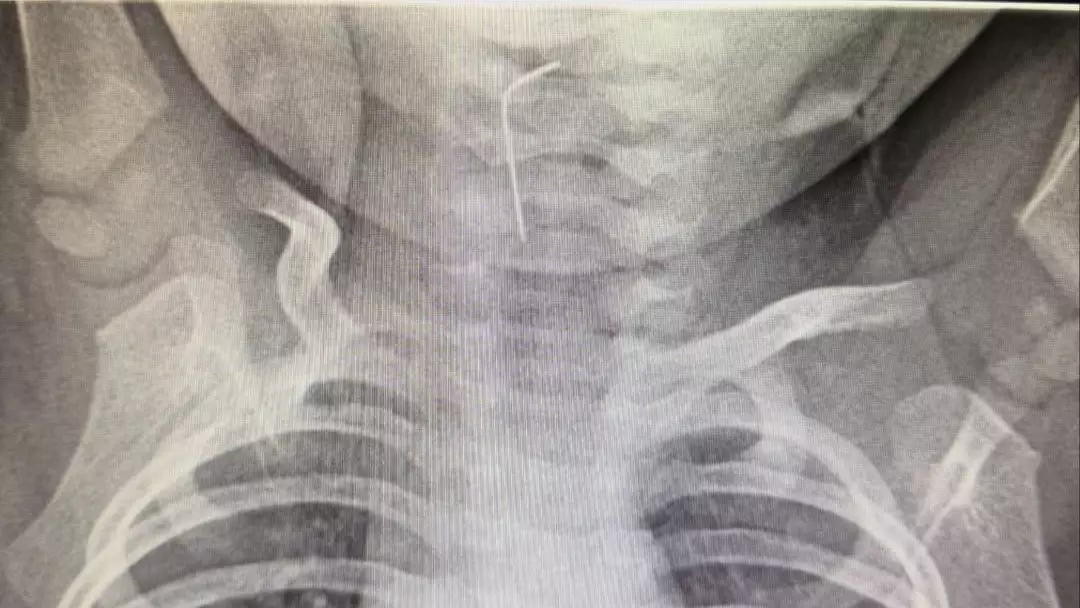

В Туркестане спасли ребёнка, проглотившего иглу